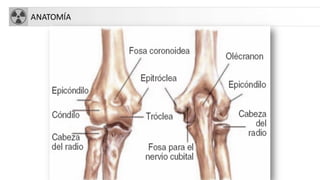

FRACTURA CODO

• Complejas a veces acompañadas de luxaciones

• Tipos:

– Supracondíleas: niños

– Trascondíleas: ancianos

– Intercondíleas: forma de T ó Y con separación de

cóndilos medial y lateral con la diáfisis

– Capitellum: fragmento libre en articulación

– Aisladas: cóndilo, tróclea, epitróclea, epicóndilo…

– Olécranon y apófisis coronoides

– Cabeza radio (30%)

ANATOMÍA